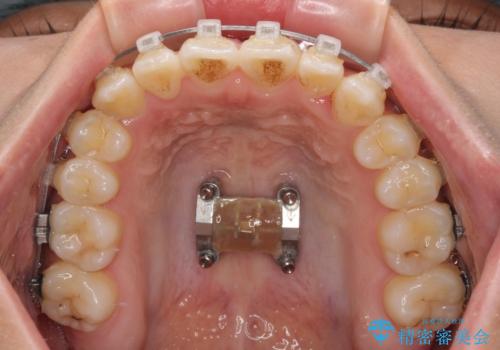

八重歯とオープンバイト 急速拡大装置を用いた矯正治療

上顎歯列が狭窄していたため、急速拡大装置により上顎骨を側方に拡大し、その後ワイヤー装置にて矯正治療を行うこととしました。

急速拡大装置で上顎骨を十分に拡大できたことで、非抜歯で八重歯を歯列に納めることができました。